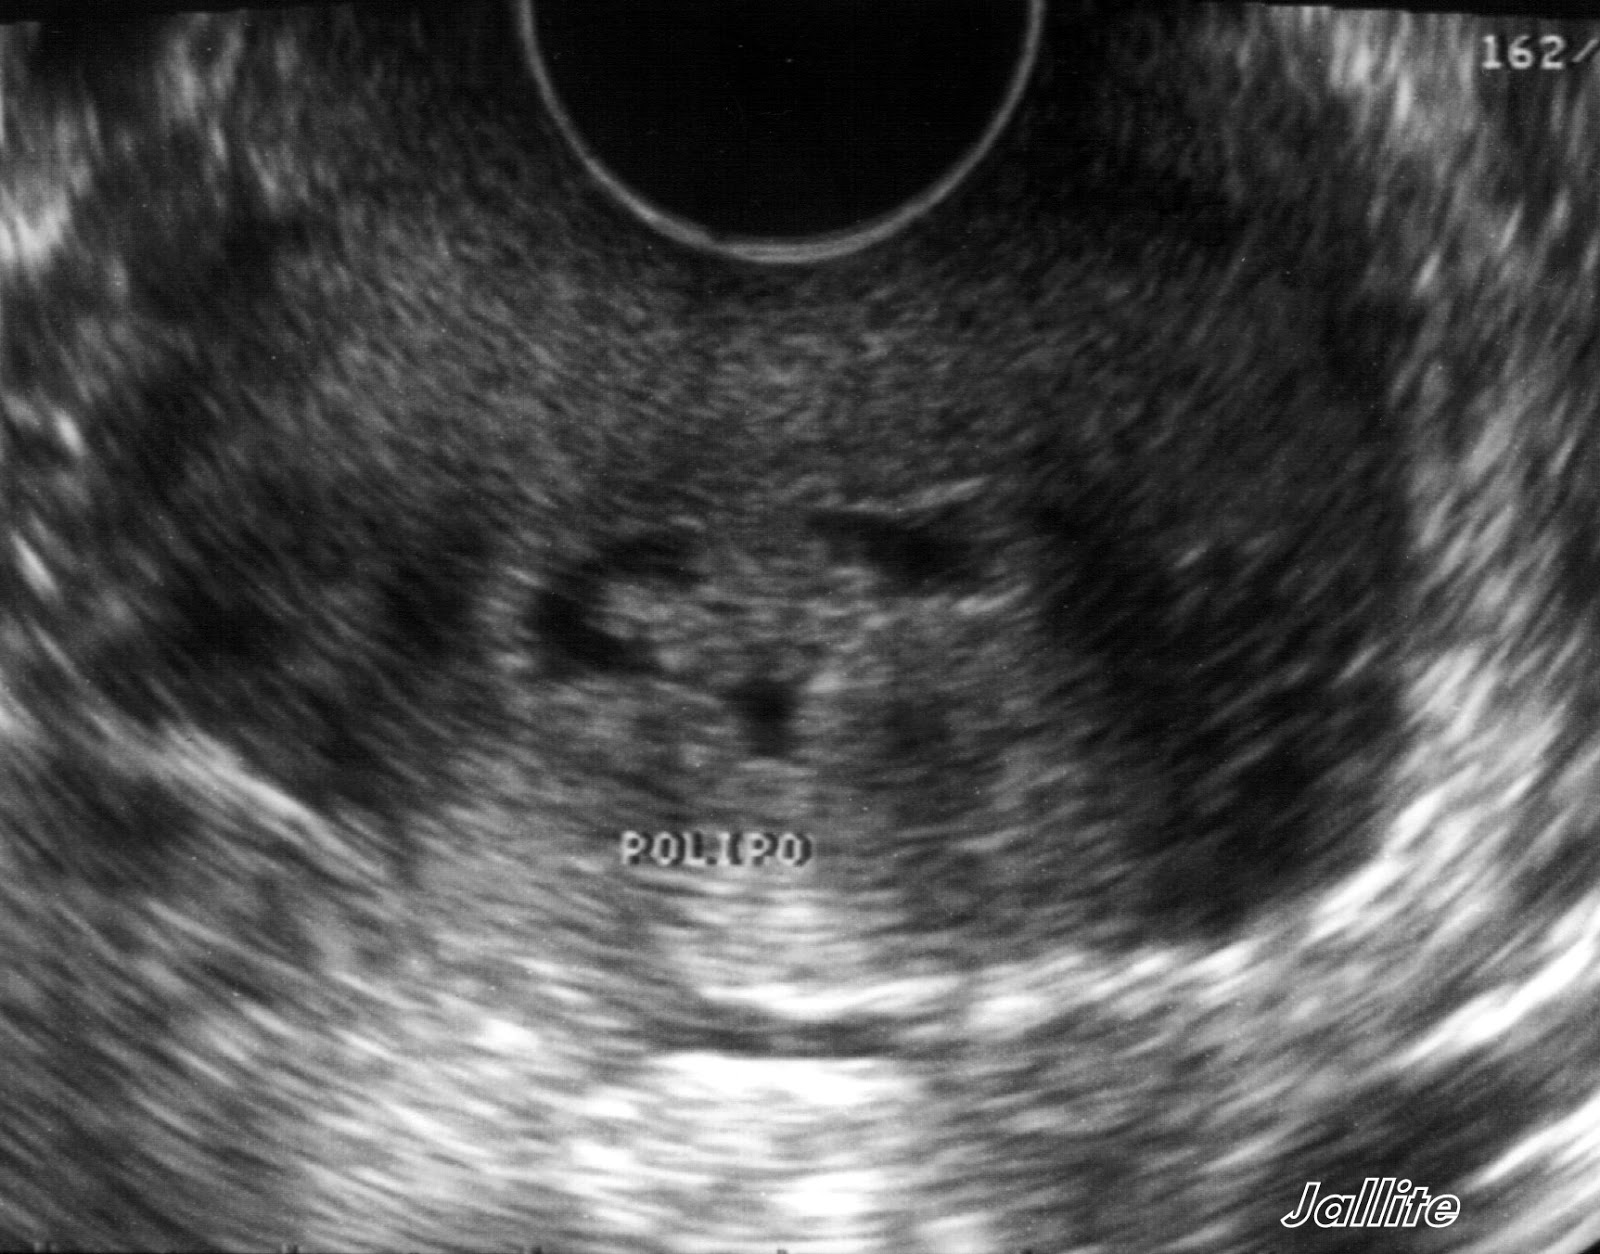

O Que Significa Pólipo Endocervical? Quando falamos em "pólipo endocervical", estamos nos referindo a esses crescimentos específicos que ocorrem no colo do útero. Geralmente, eles são benignos, mas, em alguns casos, podem se tornar malignos, o que é motivo de preocupação. Vamos discutir mais sobre esse aspecto posteriormente neste.. Há dois tipos deles: pólipo endometrial e pólipo endocervical. Neste artigo iremos explicar quais são suas características e a diferença entre eles. Os pólipos endometriais são, como o próprio nome sugere, as lesões que desenvolvem-se no endométrio e, portanto, localizam-se na cavidade uterina. Eles são constituídos a partir do.

O pólipo endometrial se caracteriza como uma saliência sólida localizada no endométrio (tecido que reveste o interior do útero), causada pelo crescimento anormal de células. O seu tamanho varia de 5 mm a 3 cm, podendo ser único ou múltiplo. Esse tipo de tumor benigno é mais comum na menopausa.. Se você recebeu recentemente um diagnóstico de pólipo no útero, fique tranquila. Na grande maioria das vezes, eles são alterações benignas com pequeno potencial de malignização. Pólipos uterinos são projeções da camada mais interna do útero, acima de sua superfície, sendo formados pelos mesmos tipos de célula, porém com um crescimento exagerado.